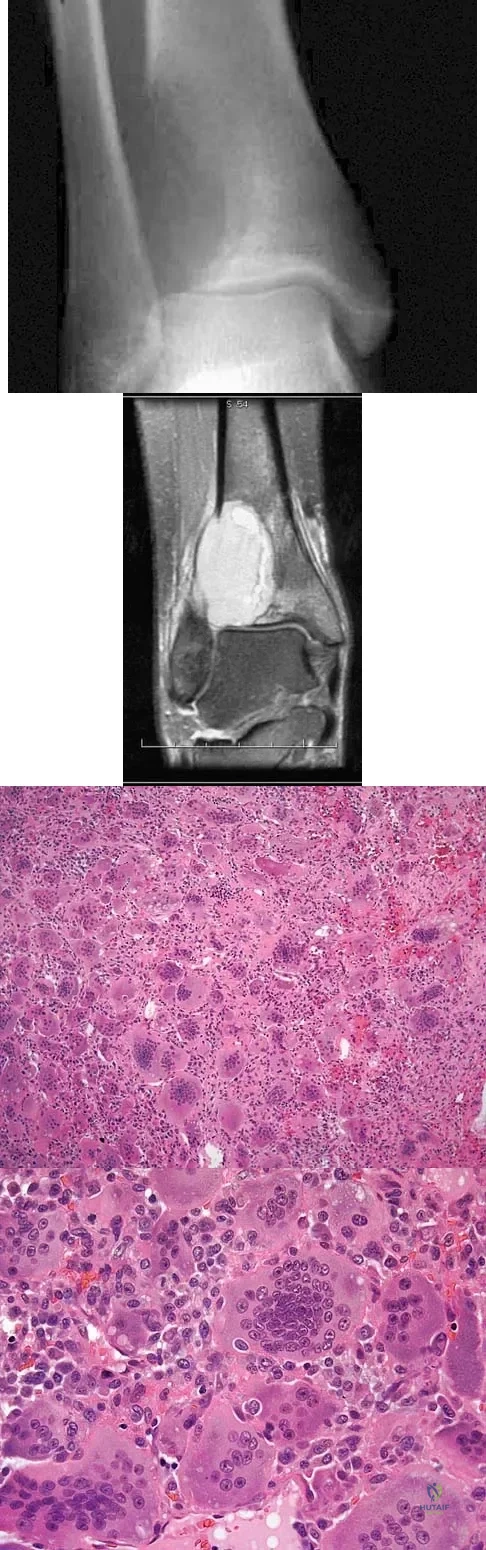

A 40-year-old man has a painless mass around his left ankle. He notes minimal growth over the past year. An MRI scan is shown in Figure 73a, and biopsy specimens are shown in Figures 73b and 73c. What is the most likely diagnosis?

Explanation

The biopsy specimen is a low-power view of a soft-tissue sarcoma with a biphasic pattern of epithelial cells and fibrous spindle cells that are typical of a synovial sarcoma. A deep, painless soft-tissue mass greater than 5 cm in size is suspicious for a sarcoma. The imaging in this patient is indeterminate and the patient requires a biopsy for an accurate diagnosis. The biopsy reveals a tumor with a biphasic appearance consistent with a synovial sarcoma. These tumors are slow growing, occur primarily in the lower extremities, and are found in a younger demographic population compared to malignant fibrous histiocytoma and liposarcoma. They can occur in a biphasic pattern with clumps of epithelial cells and fibrous spindle cells or in a monophasic pattern. Synovial sarcomas stain positively for keratin. Keratin is positive in nearly all biphasic types and in many tumors of the monophasic fibrous type. Sixty percent of these tumors are found in the lower extremity. The area around the knee is the most common location, followed by the ankle and foot. Epithelioid and clear cell sarcomas are found associated with tendon sheaths of the hand and feet and are generally smaller in size. Epithelioid sarcoma may resemble granulomatous inflammation histologically; clear cell sarcoma is composed of nests of clear cells with occasional multinucleated giant cells. Pigmented villonodular synovitis is found within the synovium and is characterized by a villous histologic appearance with hemosiderin-laden macrophages. Malignant fibrous histiocytoma has a storiform histologic pattern with an abundance of pleomorphic cells. Enzinger FM, Weiss SW: Soft Tissue Tumors, ed 3. St Louis, MO, Mosby, 1995, p 757.

References:

- Menendez LR (ed): Orthopaedic Knowledge Update: Musculoskeletal Tumors. Rosemont, IL, American Academy of Orthopaedic Surgeons, 2002, p 227.